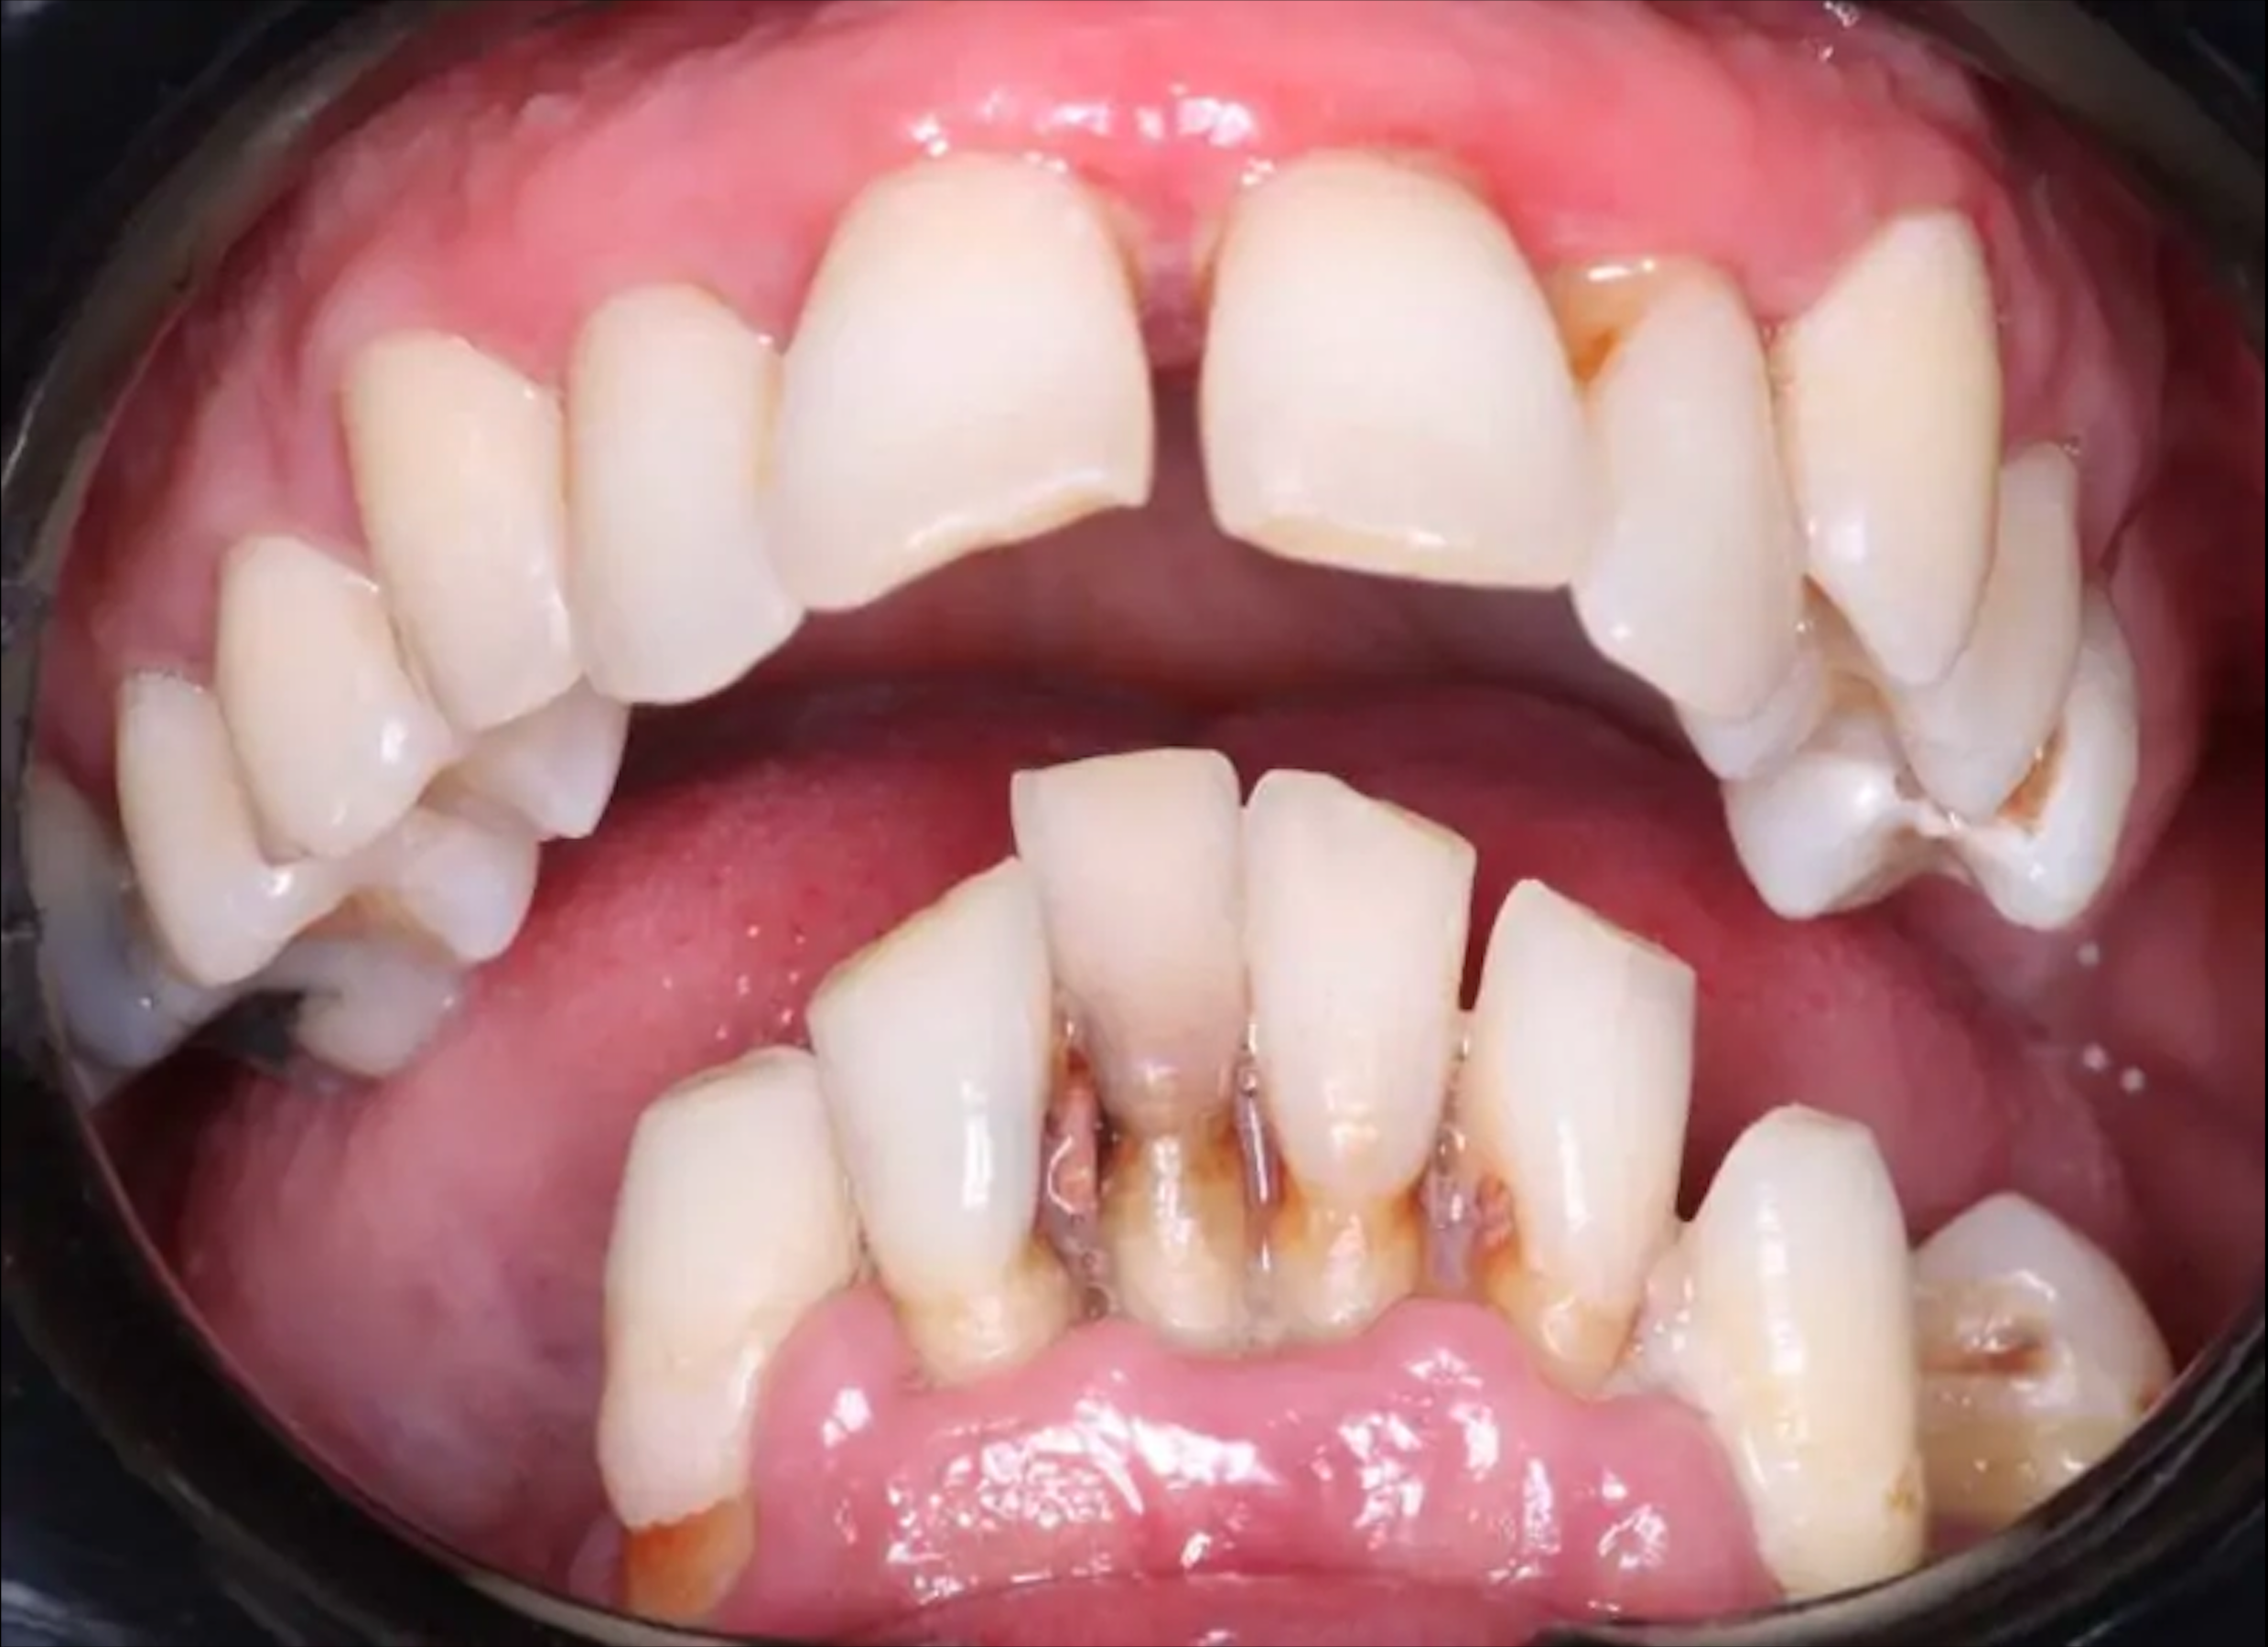

Пациент обратился к стоматологу с жалобами на боль и кровотечение.

При осмотре выявлено выраженное обширное воспаление в полости рта, связанное с подвижностью зубов нижней челюсти третьей степени. Пациент выразил желание полностью устранить боль и восстановить функциональность и эстетику в кратчайшие сроки. С

учётом результатов физикального и инструментального обследования (ОТО) и пожеланий пациента, запланировано нехирургическое пародонтологическое лечение верхней челюсти.